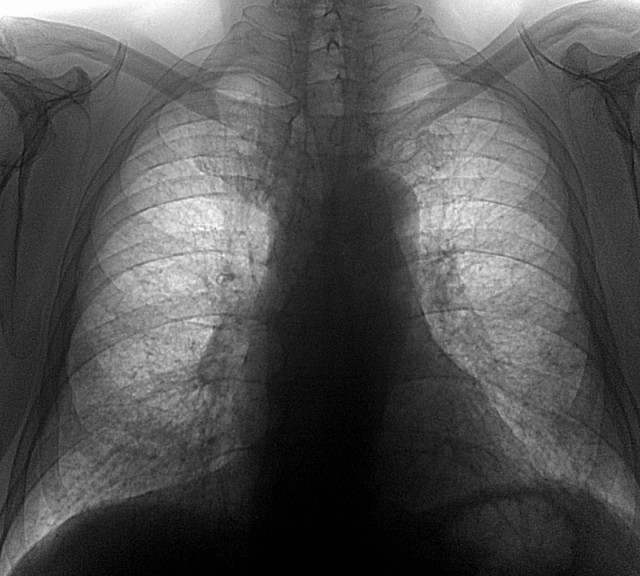

Диагностика бериллиоза осуществляется на основании анамнеза, объективного обследования, анализа крови и рентгенологического исследования лёгких. При осмотре пациента врач обращает внимание на наличие специфических проявлений дыхательной недостаточности (одышка, деформация пальцев). При проведении перкуторного обследования - выслушивается коробочный звук, который указывает на наличие эмфиземы, и ограниченность подвижности легочного края, а в нижних отделах слышны мелкопузырчатые хрипы. При проведении биохимического анализа крови можно обнаружить повышение уровня белка в сыворотке (в первую очередь за счет гипергаммаглобулинемии). На рентгене заметны диффузные интерстициальные, линейно-сетчатые или мелкопятнистые образования в лёгких.

- I стадия характеризуется преимущественно интерстициальными изменениями в лёгких (на увеличенной рентгенограмме заметны немногочисленные гранулёмы);

- II стадия - более выраженные изменения (многочисленные гранулёматозные тени);

- III стадия - увеличение количества и размеров гранулём, выраженная деформация сосудисто-бронхиального рисунка, а также образование крупнобуллёзной эритемы.